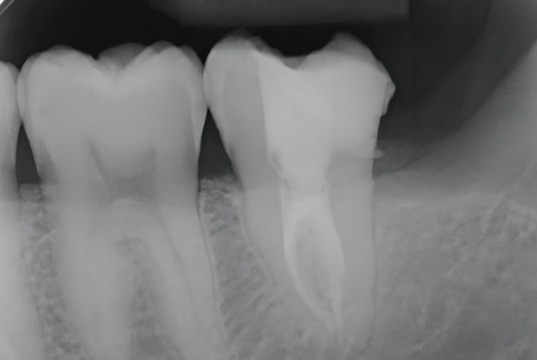

A postoperative periapical radiograph was taken to evaluate the core build-up. The UltraCore dual-cure core build-up dental restorative materials exhibited excellent radiopacity, allowing clear visualization of its margins within the access cavity.

The tooth is now ready for a cuspal-coverage restoration as the next step to restore full function and long-term durability.